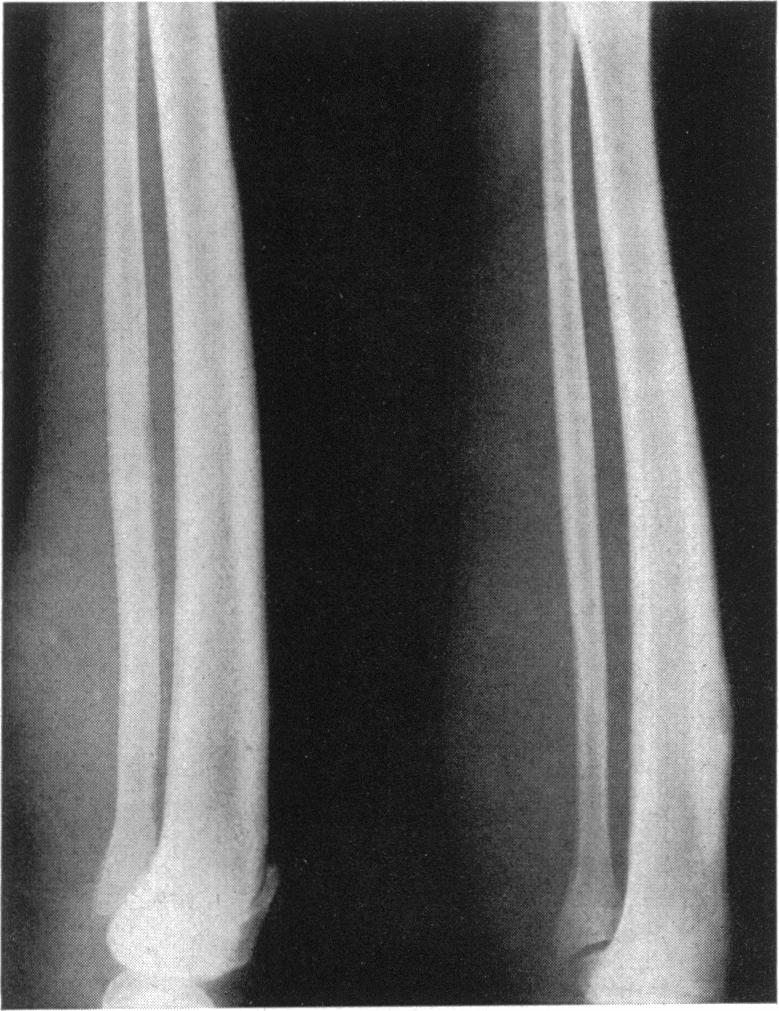

A form of endemic syphilis exists in the Bakwena Reserve of the Bechuanaland Protectorate known by the local name of "dichuchwa". It is similar to bejel, njovera and the endemic syphilis reported elsewhere in the world. The Government of the Protectorate, with the assistance of WHO and UNICEF, began in November 1953 a mass campaign in the Reserve to control this disease and, at the same time, to study its epidemiological, clinical, social and therapeutic aspects. The seropositivity rate in the Reserve was found to be 37%.Dichuchwa is a childhood and family disease, usually spread non-venereally. The early lesions are similar to secondary lesions of sporadic venereal syphilis, and are often followed by tertiary lesions affecting mainly the skin, nasopharynx and long bones. Primary lesions are rare but may occur under certain epidemiological conditions if the inoculum is sufficiently large; thus a mother may develop primary sores on the nipples through suckling an infected infant. Lesions of the cardiovascular and central nervous systems and congenital syphilis are also rare. Superinfection of an already infected and allergic host is probably the chief reason for the frequency of the tertiary lesions.Treatment of the disease with penicillin is very effective, and the authors believe that mass treatment of cases and contacts combined with an improvement in the standards of hygiene could eradicate the disease.

在贝专纳兰保护地的巴克韦纳保护区存在一种地方性梅毒,当地称之为“迪楚瓦病”。它与非性病性梅毒、恩乔韦拉病以及世界其他地方报道的地方性梅毒相似。在世界卫生组织和联合国儿童基金会的协助下,保护地政府于1953年11月在该保护区发起了一场大规模防治这种疾病的运动,同时研究其流行病学、临床、社会和治疗方面的情况。发现该保护区的血清阳性率为37%。迪楚瓦病是一种儿童和家庭疾病,通常通过非性途径传播。早期损害类似于散发性性病梅毒的二期损害,随后常出现三期损害,主要影响皮肤、鼻咽和长骨。一期损害很少见,但在某些流行病学条件下,如果接种量足够大,也可能发生;例如,母亲在哺乳感染婴儿时,乳头可能出现一期溃疡。心血管和中枢神经系统损害以及先天性梅毒也很少见。已经感染且过敏的宿主发生重复感染可能是三期损害常见的主要原因。用青霉素治疗这种疾病非常有效,作者认为对病例和接触者进行大规模治疗并提高卫生标准可以根除这种疾病。